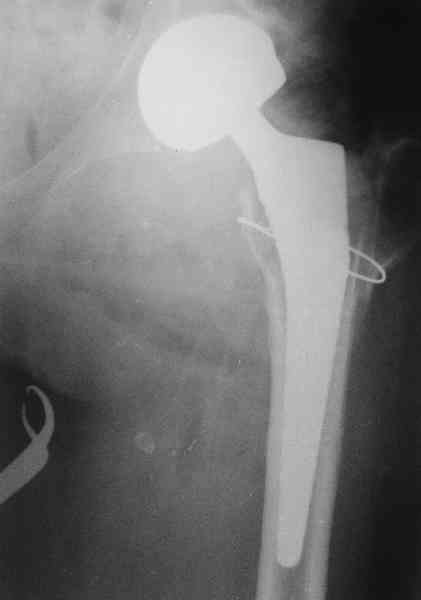

Коллеги, обещанный follow-up.

Больного прооперировали на прошлой неделе (цементный протез, цемент с гентамицином). Использовали задне-боковой доступ. В области перелома подвижности практически не было, так что тему сообщения уместно заменить на "неправильно сросшаяся шейка". И в головке, и во впадине

были значительные дегенеративные изменения, так что ни биполяр, ни остеосинтез тут неуместны (хотя это предлагали в ortopod'е). После релиза удлинили ногу на 3 см. Дальше удлинять побоялись из-за

натяжения седалищного нерва, хотя в принципе можно было бы еще 15-20 мм нарастить. По послеоперационной рентгенограмме анатомическое укорочение порядка 15 мм. Клинически при ходьбе - 4 см, но это за счет перекоса таза.

The patient underwent cemented THR on last week. Postero-lateral approach was used. There was only minimal motion at the fracture site and we had to cut the femoral head with oscillating saw. The femoral head was deformed with it's cartilage completely absent in some areas.

Acetabulum showed gross degenerative changes, especially in superior rim. So I think it was right choice not to do ORIF in this case. After some soft tissue release we've lengthened the leg up to 3 cm. Further lengthening was possible but we stopped at that moment due to tension of n. ischiadicus. Now patient walks with crutches. Leg length discrepancy is about 4 cm due to pelvic tilt (discrepancy on post-op x-ray is 15 mm).